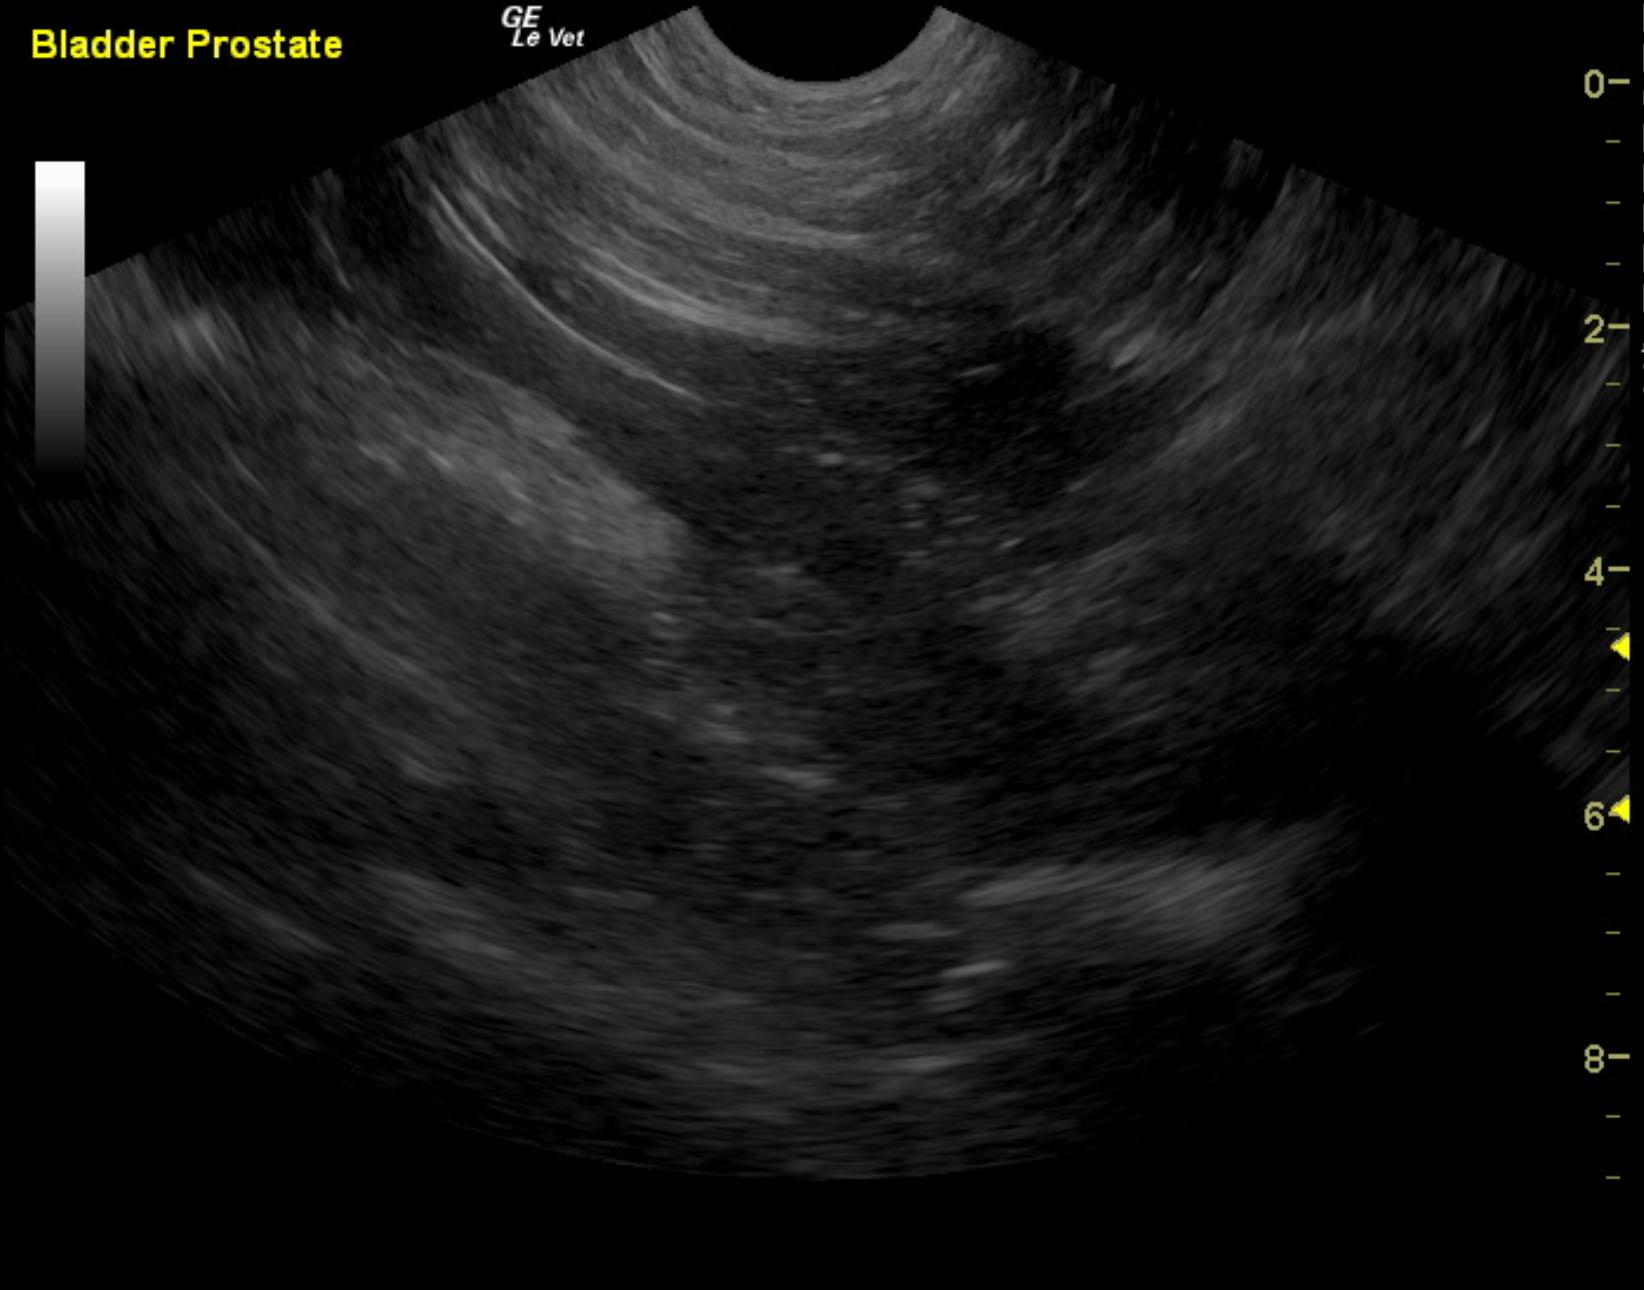

A 3-year-old neutered male Labrador Retriever dog was presented for evaluation of decreased appetite, possible polyuria and polydypsia, taking longer to urinate than normal, and hematuria. On urinalysis, isosthenuria (1.016), 3+ protein, white blood cells, and red blood cells were present. Stress leukogram was evident on CBC, but serum chemistry was within normal limits.

A 3-year-old neutered male Labrador Retriever dog was presented for evaluation of decreased appetite, possible polyuria and polydypsia, taking longer to urinate than normal, and hematuria. On urinalysis, isosthenuria (1.016), 3+ protein, white blood cells, and red blood cells were present. Stress leukogram was evident on CBC, but serum chemistry was within normal limits.